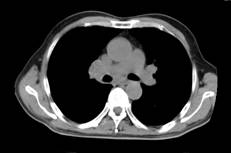

张××,男,56岁,外院CT增强示肝右叶“巨块型肝癌”,首次介入治疗后复查CT(2012年4月25日)所见瘤体大部栓塞,周围组织损伤小(图1a~b)。3年9个月后复查(2016年1月21日)见原瘤体明显缩小,上方肝实质复发病灶(图2a~b)。

图1a 图1b

图2a 图2b